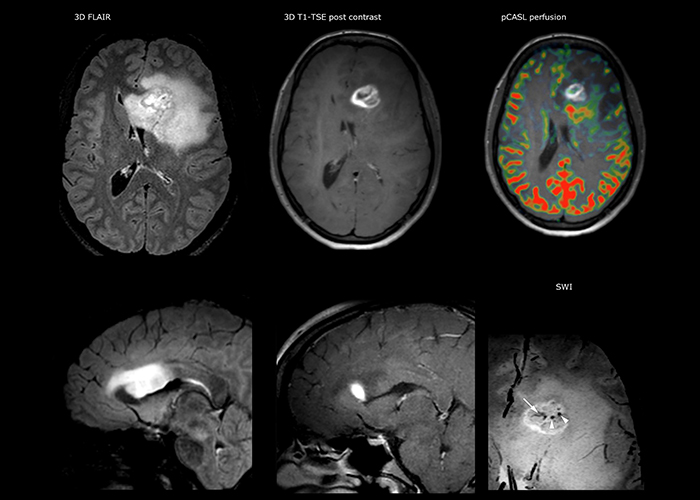

Dr. Savatovsky nutzt fünf oder sechs verschiedene ExamCards für die Bildgebung einer Raumforderung oder eines bekannten Tumors im Gehirn. „Wenn eine Raumforderung im Gehirn vorliegt, versuchen wir diese zu charakterisieren, um dem Neurologen die Informationen zur Festlegung des nächsten Schrittes zu liefern bzw. den Neurochirurgen bei der Vorbereitung eines Eingriffs oder einer Biopsie zu unterstützen. Für die Untersuchung nach einer Behandlung verfügen wir je nach Therapieform über verschiedene Protokolle und wir verfolgen spezifische Ansätze bei intra- und extraaxialen Tumoren.“ „Dies ist die umfassendste Untersuchung, die wir durchführen. Ingenia liefert aufgrund der guten räumlichen Auflösung und des hohen Signal-Rausch-Verhältnisses alle diese Daten. Außerdem ist das System so flexibel, dass damit kürzere Sequenzen möglich sind. Somit sind wir in der Lage, eine sehr umfangreiche Untersuchung in begrenzter Zeit vorzunehmen.“

„Die größte Herausforderung besteht in der sachgemäßen Charakterisierung der Läsion und der angemessenen Information des Chirurgen, zum Beispiel was die Position der Gefäße und der funktionellen Bereiche betrifft. Gelegentlich ist eine sehr umfassende Untersuchung notwendig, beispielsweise wenn eine Raumforderung an einem anderen Krankenhaus festgestellt wurde und der Patient anschließend an uns überwiesen wurde. Wir führen dann eine Charakterisierung der Läsion und eine präoperative Bildgebung in einer Untersuchung durch, d.h. sowohl eine morphologische als auch eine funktionelle Beurteilung. Für die morphologische Beurteilung verwenden wir eine T1-gewichtete Prä- und Postkontrastbildgebung sowie FLAIR für die Beurteilung der Infiltration und Diffusion. Für die funktionelle Charakterisierung führen wir eine Perfusionsbildgebung, eine MR-Spektroskopie und eine suszeptibilitätsgewichtete Bildgebung durch, um Mikrogefäße oder Mikroblutungen innerhalb der Läsion aufzuspüren[4]. Für die präoperative Untersuchung führen wir eine spezifische morphologische Bildgebung durch, die mit dem Navigationssystem kompatibel ist. Je nach Position des Tumors erfolgt fMRT oder TDI.“